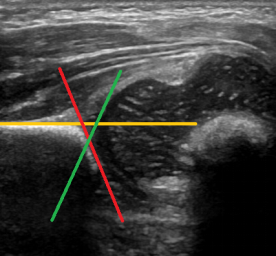

目前,超声是检查DDH应用最广泛的手段,国内很多地区都开展了小儿髋关节超声筛查工作。超声筛查可于出生后至6个月进行,这也是检查的黄金时期。超声检查可观察髋关节的髋臼与股骨头发育及对位情况,并对骨顶及软骨顶测量,通过观察与测量评估髋关节类型,从而做出髋关节发育是否正常的判断。